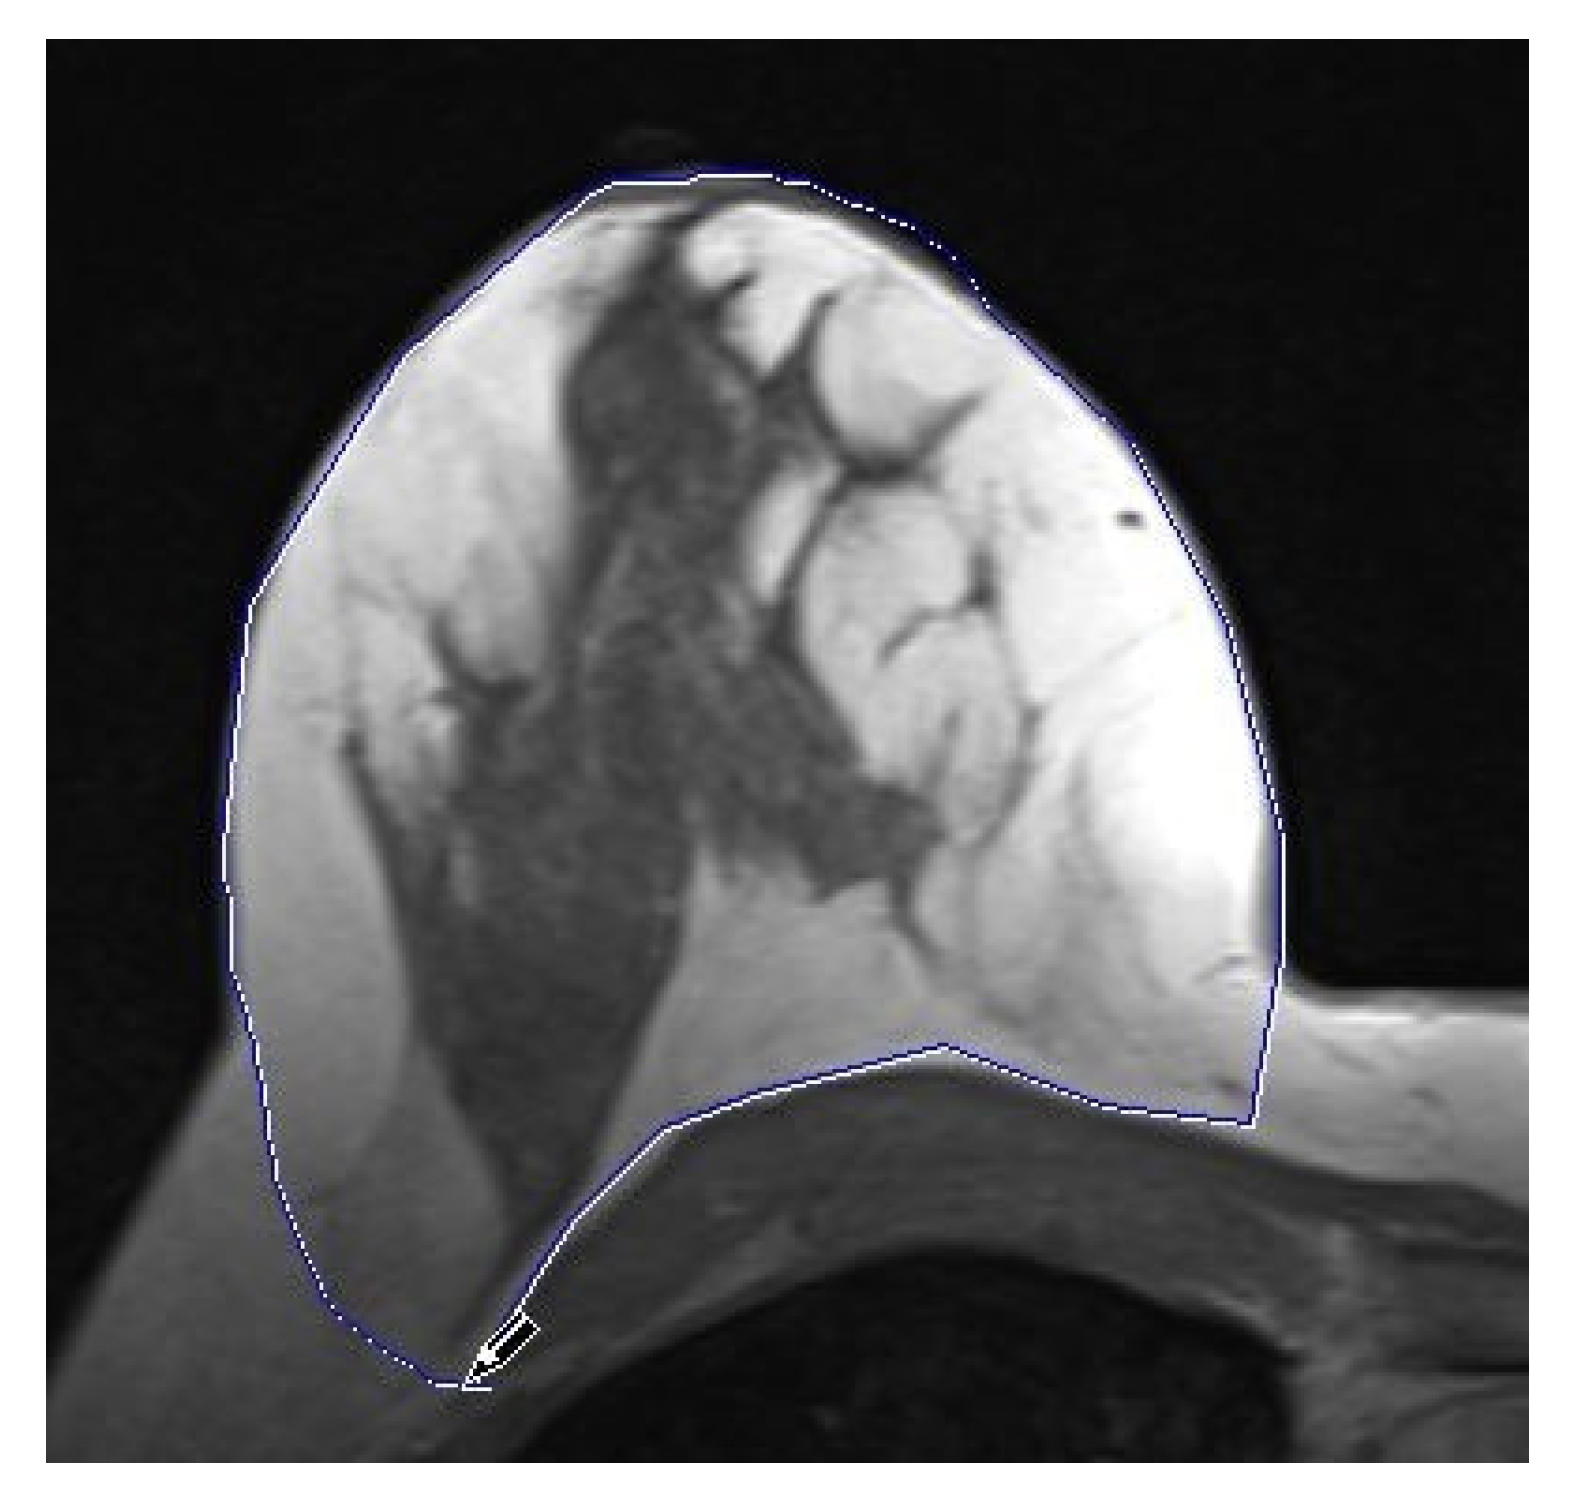

- Residual glandular tissue in retromamillary area;

- Residual glandular tissue at other location;

- Volume of the residual glandular tissue.